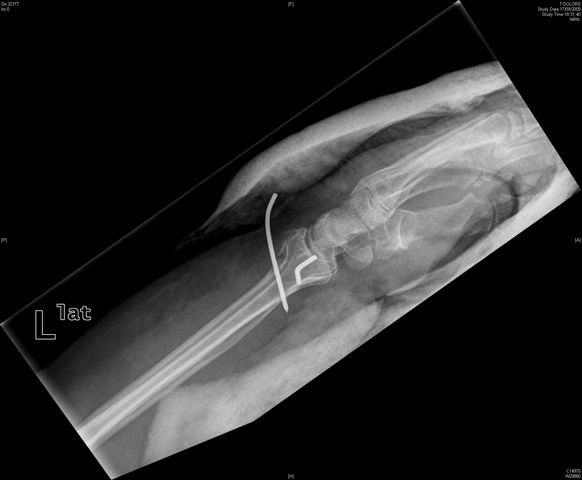

Tratamiento de fractura de radio con agujas.

Tratamiento con agujas de fractura de radio.